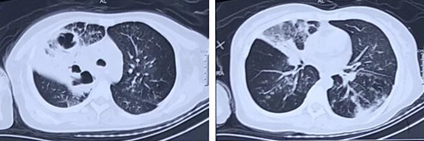

患者入院前2周感冒受凉后出现胸背部钝痛伴轻度呼吸困难,未在意,自服“感冒药”无好转。10天前呼吸困难进行性加重,胸部CT提示右肺上叶斑片状渗出影伴实变,内有少许空洞,中叶部分实变(图1)。当地医院给予头孢噻肟抗感染治疗3天,呼吸困难持续加重,后出现Ⅱ型呼吸衰竭伴意识障碍、发热。外院给予气管插管联合呼吸机辅助通气,同时将抗感染药物调整为亚胺培南西司他丁+利奈唑胺治疗4天,患者病情改善不明显,遂转入我科。自发病来患者精神、饮食、睡眠差,二便正常,体重减轻约5 kg。

图片

图1  患者胸部CT